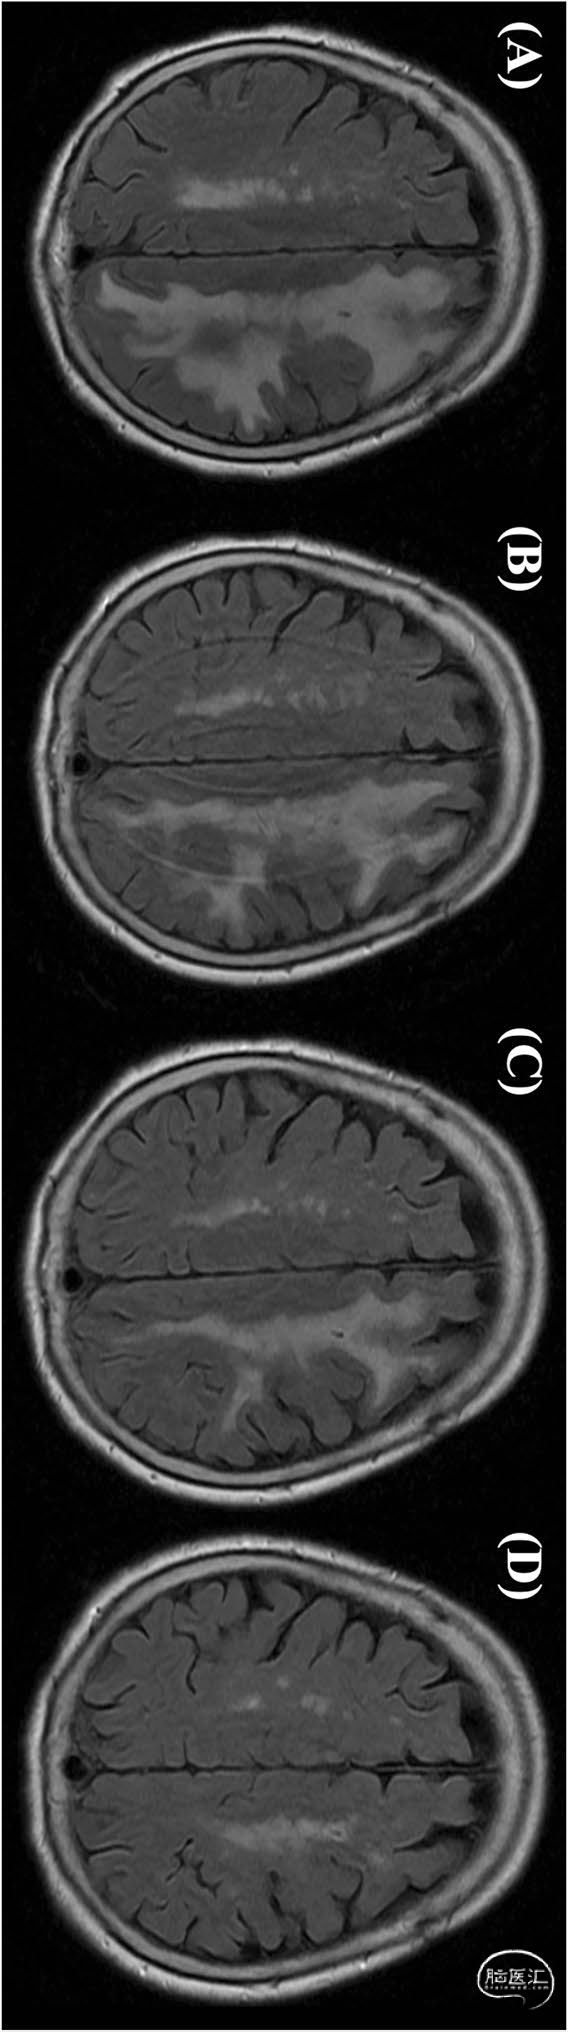

图2,FLAIR成像的脑水肿演变。A,术后3个月的FLAIR成像。B,连续3天类固醇脉冲击治疗后,脑水肿轻度减轻。C,激素冲击治疗1个月脑水肿明显减轻。D,激素冲击治疗后2个月脑水肿完全缓解:

随后因失语症再次入院,MRI和MRA发现T2异常高信号加重,但没有新的缺血性病变。怀疑迟发性白质脑病。患者接受类固醇脉冲击治疗,言语和书写困难的显著改善。复查MRI显示T2异常信号明显减少,持续性改善所以逐渐降低和停用口服类固醇。在6个月的随访中,MRI证实信号异常完全消失(图2)。